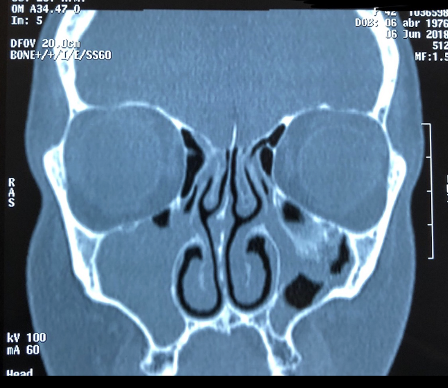

IMAGEN DE OCUPACIÓN PARCIAL EN SENO MAXILAR DERECHO DE UN 30% DE OCUPACIÓN. PERIFERICO, MARGINAL. CONDESVIACIÓN SEPTAL A LA DERECHA DE CONFORMACIÓN ÓSEA (PORQUE SE VE BLANCO)

SE OBSERVA HIPERTROFIA DE CORNETE INFERIOR IZQUIERDO. SUPERFICIE FESTONEADA: DEGENERACIÓN PÓLIPOIDEA.

CONCLUSIÓN: SINUSITIS MAXILOETMOIDAL BL, DESVIACIÓN SEPTAL E HIPERTROFIA DE CORNETE INFERIOR IZQUIERDO CON DEGENERACIÓN POLIPOIDEA.